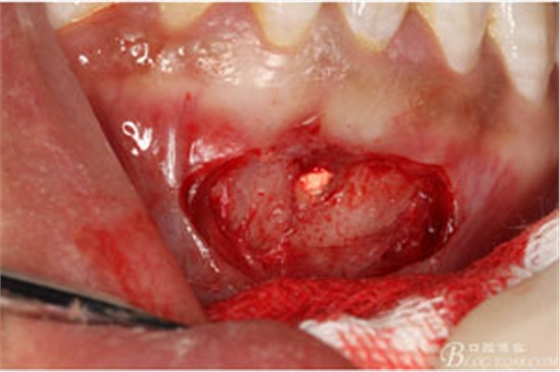

圖7.局部麻醉下,行下前牙唇側(cè)弧形切口,翻瓣可見31唇側(cè)骨壁有缺損,并有根充物暴露